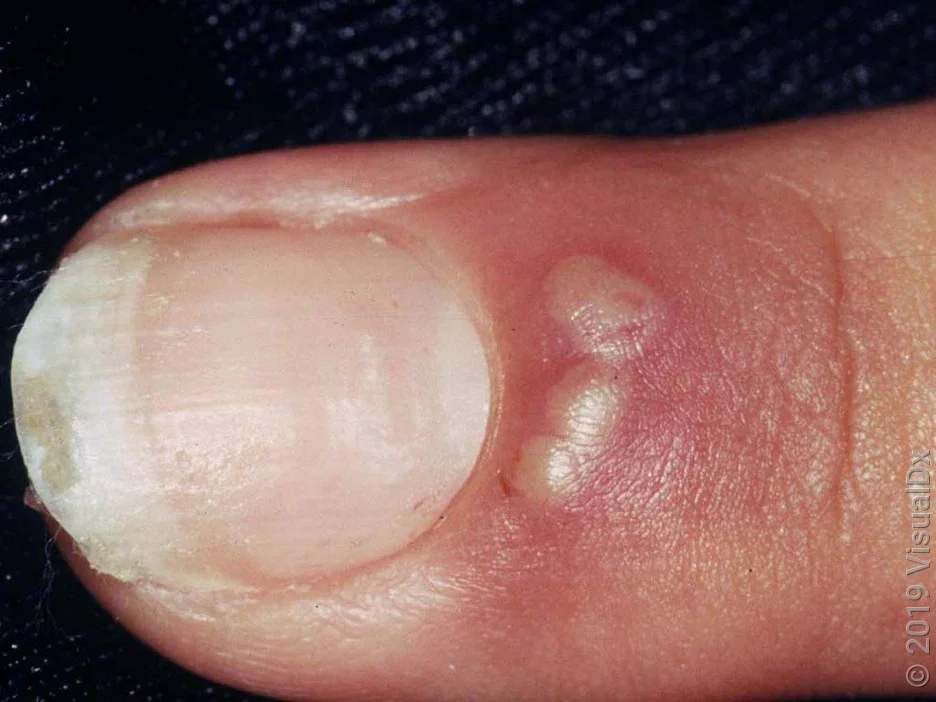

Nail bed infection pictures

Here are some pictures to help you identify signs of a nail bed infection.

Pus- or fluid-filled blisters

Red or violet discoloration at the nail fold, which can extend down the finger or toe

Swelling around the nail